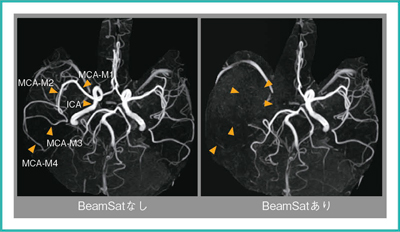

抑制効果の評価

BeamSatパルスによる血流信号の抑制範囲と抑制率を調べた。BeamSatの位置は上記の基準で設定し,BeamSatパルスあり,なしの2回撮像した。使用装置は1.5T MRI(日立メディコ社製),受信コイルは8ch Head,3D TOFの撮像条件はTR/TE=46.2ms/6.9ms,撮像マトリックス512×224である。取得した素画像で,ICA〜MCA-M4の各位置で信号強度を計測した。計測した信号強度を表1に,撮像結果(MIP像)を図5に示す。BeamSatなし(通常のTOF)では末梢になるほど信号強度が低下しているが,BeamSatありでは末梢になるほど信号強度が上昇している。これは,ICAで抑制された磁化が,末梢に移動するに従ってT1緩和で信号が回復している様子を示していると考えられる。また,MCA-M4 になると,背景である脳実質よりも血液の信号値が大きくなっており,MIP画像においてMCA-M4がわずかに視認できることと一致している。

以上の結果より,血流速にも依存するがICAを抑制した場合,MCA-M3程度まで安定的に抑制できることがわかった。

表1 ICA~MCA-M4の信号強度(健常例)

図5 BeamSat TOF画像(健常例)

BeamSatあり(右)では,ICAからMCA-M3は視認できない程度に抑制できているが,MCA-M4はわずかに視認できる。

また,左MCAと後大脳動脈が,BeamSatありとなしで描出能はほとんど変化していないことがわかる。

*本画像は,撮像目的・意義を説明し,文書による同意を得た健常人ボランティア画像である。